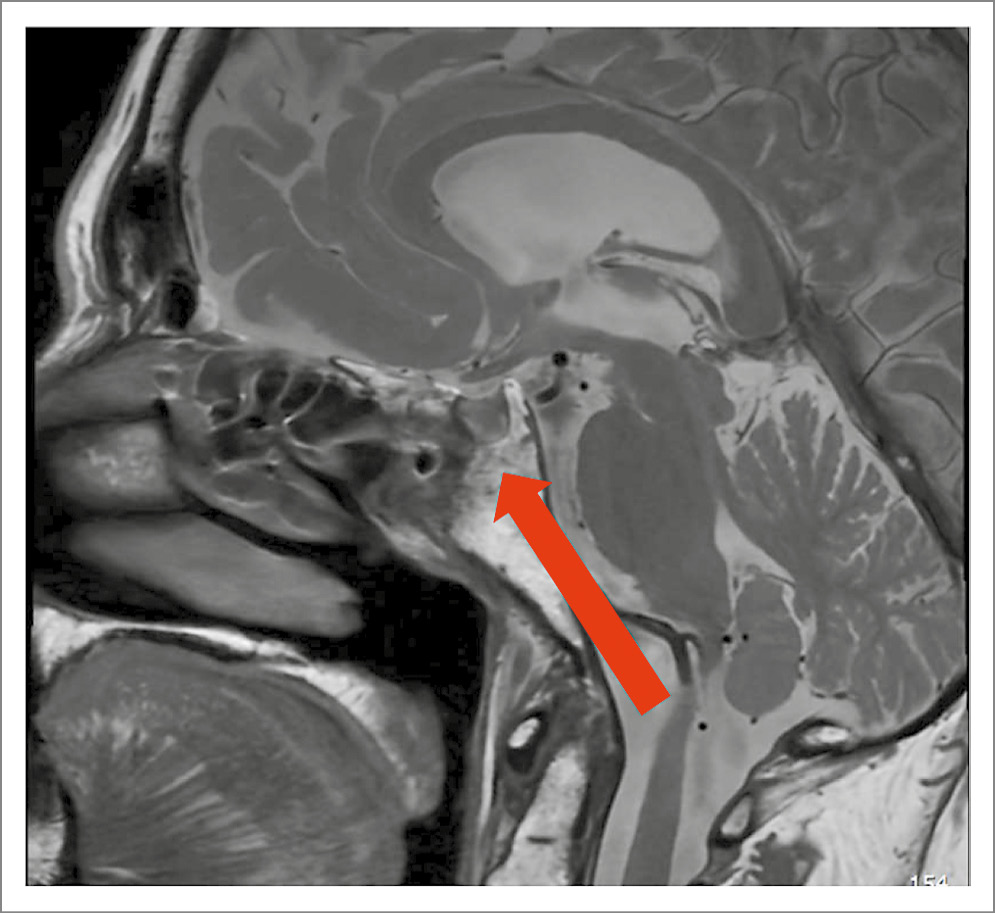

В январе 2025 г. (62 года) госпитализирована в клинику эндокринологии УКБ №2 ФГАОУ ВО «Первый МГМУ им. И.М. Сеченова» (Сеченовский Университет) с жалобами на выраженную мышечную слабость, прогрессирующее снижение мышечной массы в руках и ногах, снижение работоспособности, сниженный фон настроения, боли в грудном и поясничном отделах позвоночника. При объективном осмотре обращали на себя внимание перераспределение подкожно-жировой клетчатки по центрипетальному типу (индекс массы тела – 34,8 кг/м2), гиперемия щек, снижение мышечной силы в конечностях. По результатам лабораторного обследования подтверждена персистенция БИК: уровень свободного кортизола в суточной моче – 67,5 мкг/сут (1,5–63), кортизол в ночном подавляющем тесте с 1 мг дексаметазона – 179 нмоль/л (< 50). Уровень АКТГ снизился до 7,8 пмоль/л (< 10 пмоль/л). При проведении большой дексаметазоновой пробы получено снижение кортизола на 80% от исходного уровня (кортизол в 8:00 исходно – 662 нмоль/л, кортизол в 8:00 после приема 8 мг дексаметазона – 132 нмоль/л). По данным МРТ головного мозга – послеоперационные изменения передне-нижних отделов гипофиза, селлярной области и основной пазухи (рис. 3).

Рис. 3. МРТ головного мозга от 17.01.2025: послеоперационные изменения.

Учитывая неэффективность хирургического лечения, пациентка направлена на проведение стереотаксической радиохирургии (СРХ – гамма-нож). На этапе подготовки к СРХ возобновлена терапия кетоконазолом 400 мг/сут. Продолжены АГТ, ГЛТ, АРТ.